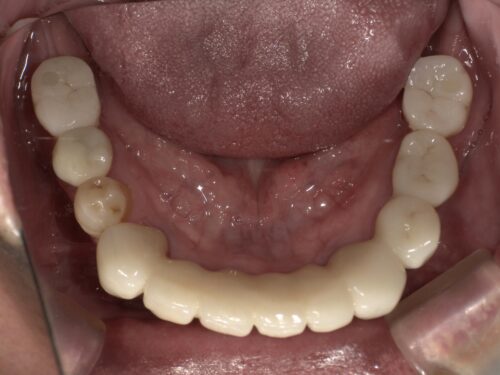

治療後の写真です。

前歯はブリッジとよばれる治療法で治しました。

根元の歯ぐきは赤みがなくなり健全な状態になりました。

奥歯でもしっかり噛めるようにすることで前歯にかかる負担を軽減しています。

前歯の傾きも改善して、上下の前歯が本来の位置関係で噛めています。

ただ、歯周病の影響で歯ぐきが下がっており、そこのブラッシングはしっかり続けていく必要があります。

歯一本一本だとグラグラしてしまうような状態でも、

ブリッジといってかぶせ物でつなぐことで全体として強度が上がるようにしています。

下の奥歯はインプラントを入れることで噛める範囲を増やしています。